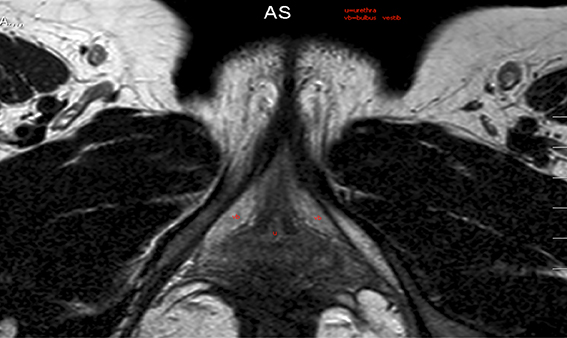

The demand for reconstruction of mutilated female genitalia is increasing in Europe due to the empowerment of immigrant and naturalised women from Africa. Their wish for reconstruction is more than a matter of surgery, as these women still have to...